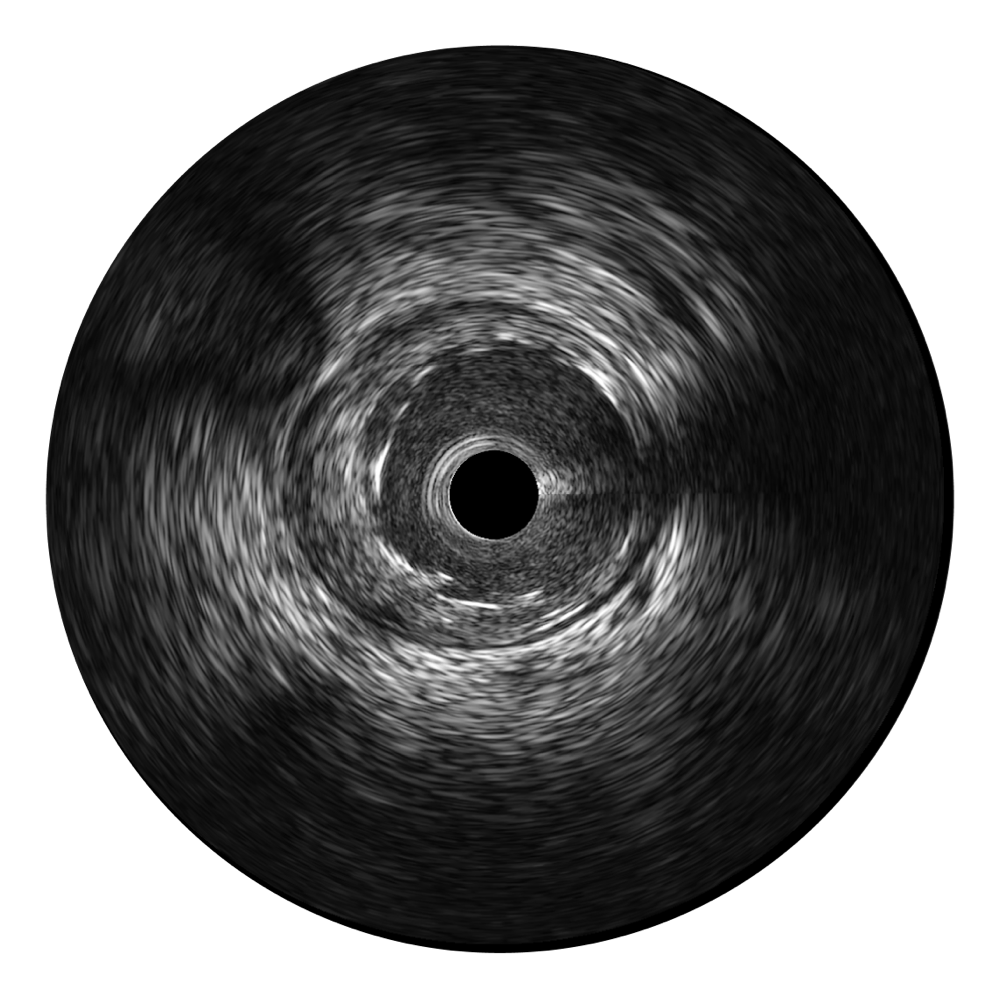

• 16877太阳集团宽频IVUS图像

• 传统IVUS图像

对比传统IVUS导管成像,16877太阳集团宽频IVUS图像的近场支架梁显影更细腻,远场中膜外血管仍清晰可辨,兼顾远中近,兼顾分辨力与穿透深度